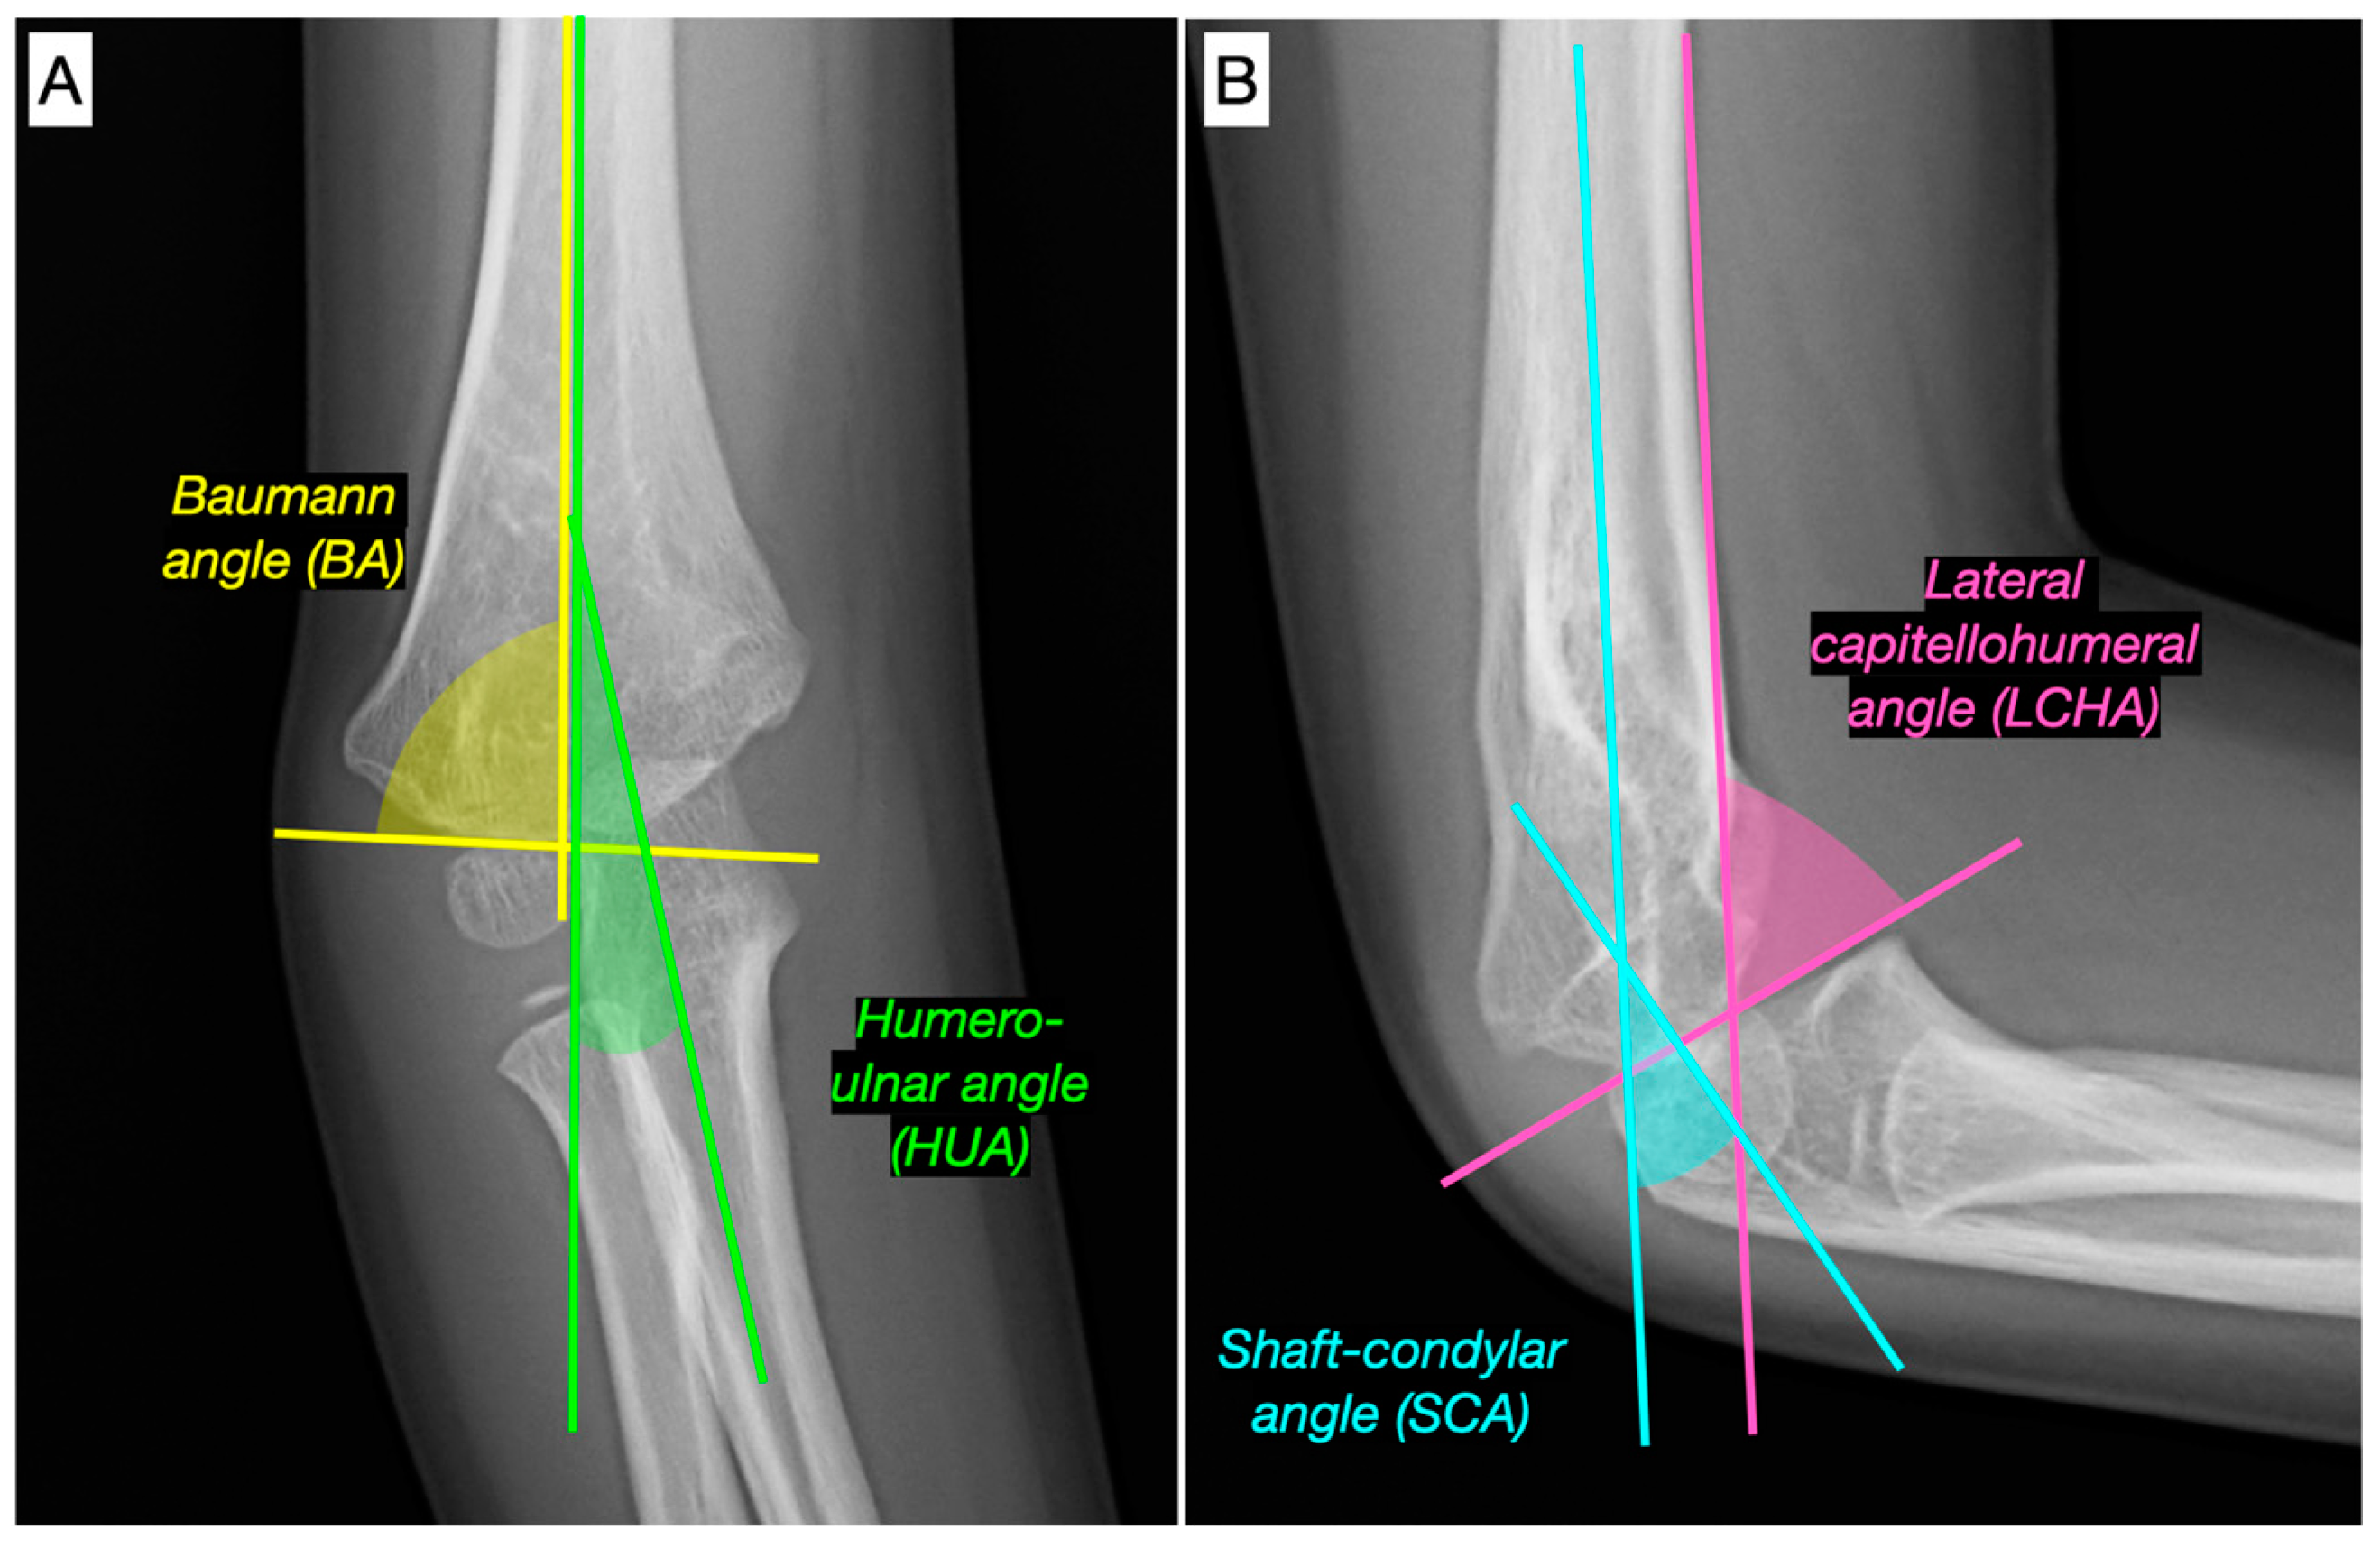

- Goldfarb, C.A.; Patterson, J.M.M.; Sutter, M.; Krauss, M.; Steffen, J.A.; Galatz, L. Elbow radiographic anatomy: Measurement techniques and normative data. J. Shoulder Elb. Surg. 2012, 21, 1236–1246. [Google Scholar] [CrossRef]

- Shank, C.F.; Wiater, B.P.; Pace, J.L.; Lee, J.; Thomas, J.; Schmale, G.; Bittner, G.; Bompadre, V.; Stults, J.; Krengel, W. The lateral capitellohumeral angle in normal children: Mean, variation, and reliability in comparison to Baumann’s angle. J. Pediatr. Orthop. 2011, 31, e266–e271. [Google Scholar] [CrossRef] [PubMed]

- Kasser, J.R.; Beaty, J.H. The Elbow Region: General Concepts in the Pediatric Patient. In Rockwood & Wilkins’ Fractures in Children; Beaty, J.H., Kasser, J.R., Eds.; Lippincott Williams & Wilkins: Philadelphia, PA, USA, 2006; pp. 529–541. [Google Scholar]